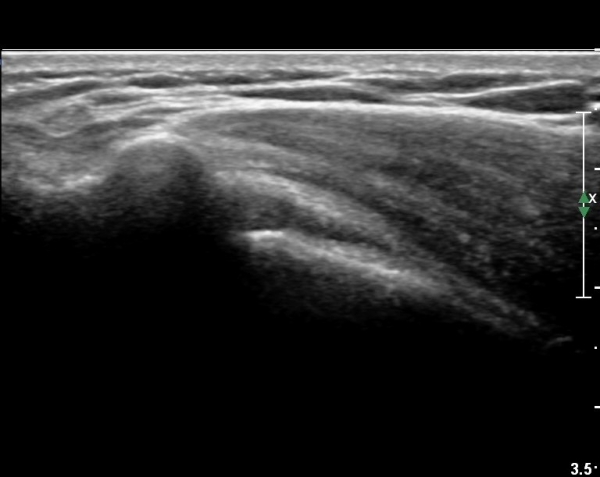

ŽÃËÀÚ¸¦ ¾à°£ °ßºÀ ¸»´ÜÀ¸·Î ³»¸®³ª ¿À±¸µ¹±â°ßºÀÀδëÀÇ ¼®È¸È­°¡ °üÂûµÈ´Ù(»çÁø 2).